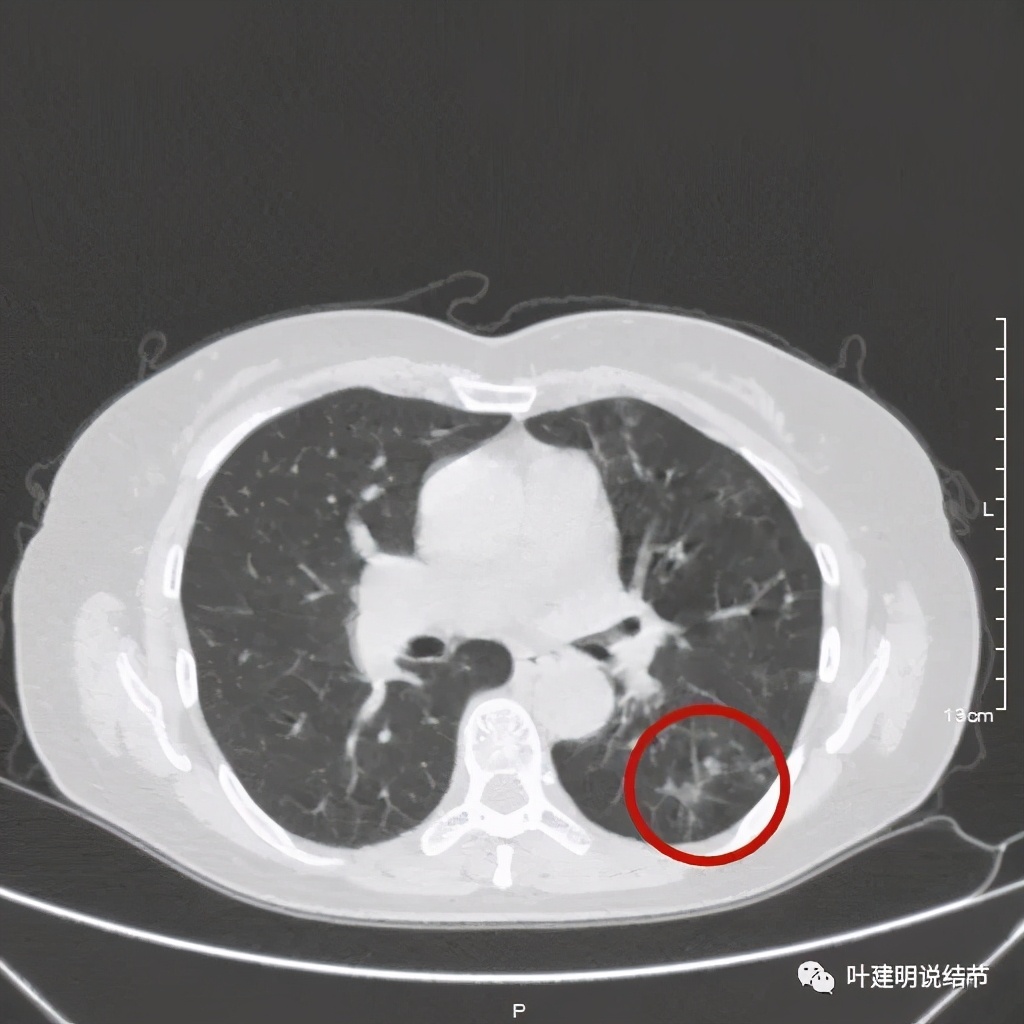

金华的某A,女性,56岁,去年8月份检查发现左肺下叶结节,是实性的,还中间有个空洞,我们说若磨玻璃结节伴空泡或空腔多为恶性范畴的,实性的也是可能性会大一些,但不如磨玻璃确切,因为结核、感染等也会类似的。我们先来看她当时的CT图像:

左下结节与血管关系密切,此层似磨玻璃结节,还夹在小血管之间,其中有血管紧贴病灶,略迂曲